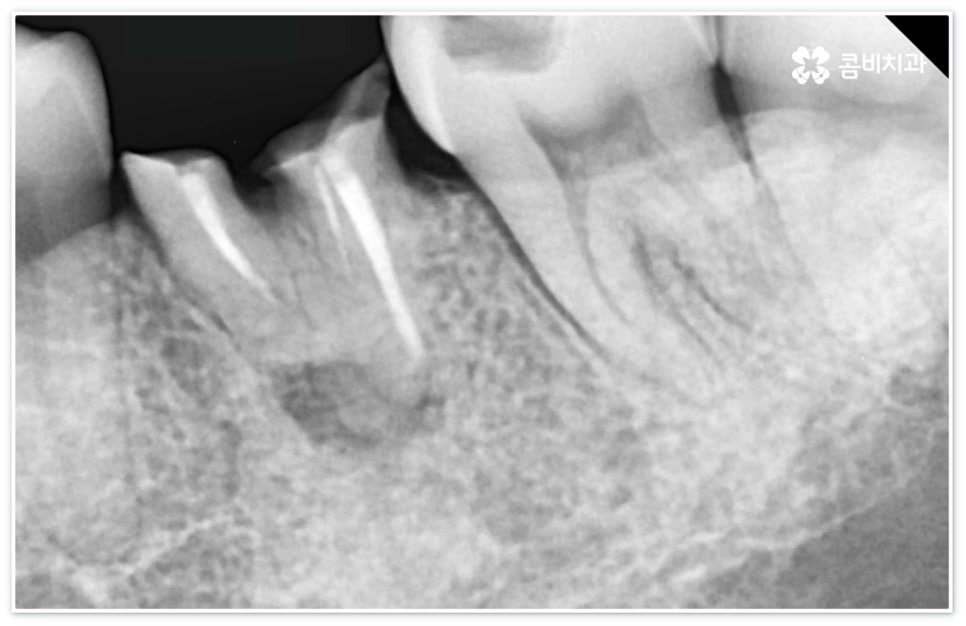

신경치료는 일견 간단해 보일 수 있으나 사람의 신경이 매우 얇고 또한 환자분들마다 신경관의 개수와 모양이 다 다르기 때문에 오염된 부위를 끝까지 깨끗하게 제거하기 위해서는 매우 섬세하고 뛰어난 기술력을 요하므로 다양한 임상 경험을 통해 풍부한 노하우를 가지고 있는 의료진과 함께 하실 필요가 있습니다.

신경치료는 오염된 치수 조직을 제거하여 감염이 더이상 진행되지 않도록 하고 치과용 충전재로 내부를 빈틈없이 채운 후 크라운 보철물을 씌워 남아있는 자연 치아를 쓸 수 있도록 하는 치료이기 때문에 그 과정에서 치아 깊숙한 곳까지 기구로 파고들어 가므로 주변 치아 조직이 예민해지면서 치료 후 며칠에서 길게는 몇 주까지 신경치료통증 을 느끼실 수 있는데요.

혹여 미세한 부근관의 염증을 놓치거나 사후 외부 원인으로 2차 감염이 일어나는 경우 신경치료통증 이 오래 지속될 수 있으니 며칠이 지났음에도 욱신거림이 줄어들기는 커녕 점차 심해진다는 느낌이 있다면 다시 한 번 치과로 내원하셔서 꼼꼼하게 검진 후 필요한 치료를 받으시는 게 좋을 거예요. 상황에 따라 재신경치료를 진행해야 할 수도 있고 좀 더 지켜보면서 발치가 불가피하지는 않은지 신중하게 판단해야 할 수도 있는데요. 예를 들어 만약 신경치료통증 의 원인이 치료 전부터 치아 뿌리에 생겼던 미세한 균열 때문이라면 치료 받은 치아로 씹을 때 통증이 지속적으로 나타날 수 있고 재신경치료 등으로 이를 살릴 수 없으므로 이 통증이 일상생활에 큰 영향을 주지 않을 경우 최대한 사용하는 데까지 사용을 하다가 임플란트 치료를 권장 드리고 있으나 증상이 심할 경우 바로 발치를 해야 하며, 매우 낮은 확률이긴 하지만 신경관 내부 뿐 아니라 외부에도 세균 군집이 생겨 치아 뿌리 끝 염증이 나아지다가 다시 악화된 상황이라면 역시 약 처방 등으로 신경치료통증 을 잡을 수 없고 발치 후 임플란트 식립을 통해 치료해야 할 거예요.